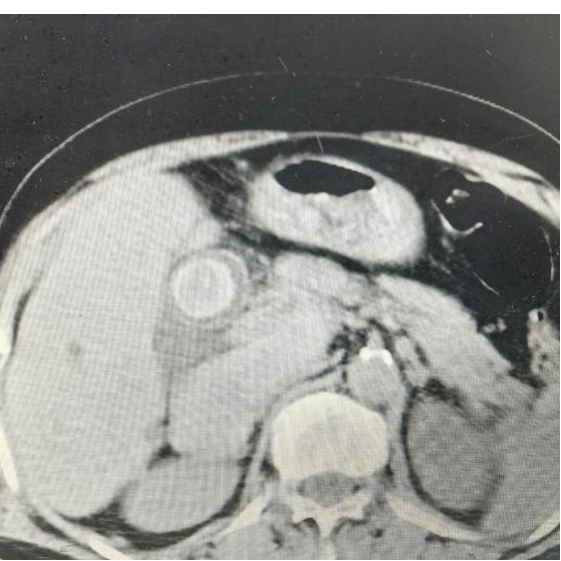

术前磁共振显示

主刀医生沿右肋缘做了个切口、逐层切开入腹探查——胆总管囊状扩张,结石像一座微型石林,层层叠叠卡在胆总管及肝内胆管,有的已经跟胆管壁长在一起,左半肝部分纤维化萎缩。团队果断进行手术:左半肝直接切除,这叫解剖性肝叶切除,沿肝脏天然分界线精准切割,该留的一寸不多切,该去的毫不含糊;胆囊一并拿掉;接着进行胆总管探查取石,随着取石钳将结石一颗一颗清理干净,术中探测oddi括约肌失能,于是同时行胆肠内引流,胆总管与空肠吻合改道手术,最后T管引流。